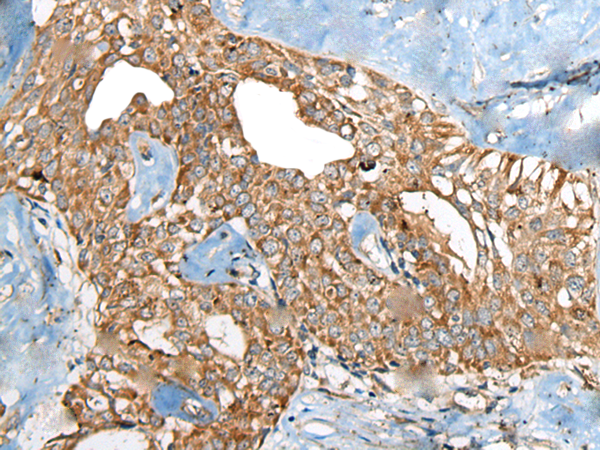

IHC positive control:

Human thyroid cancer

IHC Recommend dilution:

50-300